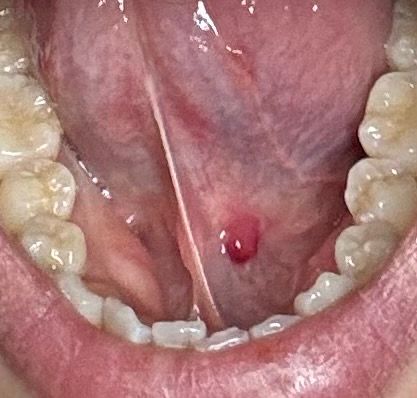

혓바닥 뭐가 났는데 밑에 이게 뭘까요??

혀 밑에 뭐가 느껴져서 처음엔 종기같이 나더니 방금 보니 피가 찬거같이 생겼네요

짜면 아플거 같은데 어디 병원을 가야할까요????

• 1번 째 사진

사진으로 봤을 때는 혈액종이나 점액종으로 보입니다. 혈액종이나 점액종은 점막 안에 혈액이나 점액 물질이 차서 생기는 증상입니다. 해당 부위가 강하게 자극될 때 생기기 때문에 점막 조직에 자극이 줄어들게 하는 것이 좋습니다.

내버려두면 나중에 자연적으로 없어집니다.

자세한 확인을 위해서 병원에서 진료를 받아보는 것을 권유드립니다.

혈종인데 굳이 짤 필요는 없고요. 1~2주면 괜찮아질 가능성이 높습니다. 그래도 구강내과를 한번 가보시면 좋을 것 같습니다.

짜시면 안되고 사진만 보았을 때에는 피가 고여서 생긴 작은 크기의 혈종이나 혈관기형 또는 타액저류로 생긴 점액류에서 자극으로 인해 피가 찬 것 등으로 추정됩니다. 임의로 건드렸을 시에는 다른 문제 생길 수 있으므로 건드리시지는 마시고 치과 구강악안면외과 또는 구강 내과 등 내원하시기를 권유드립니다.